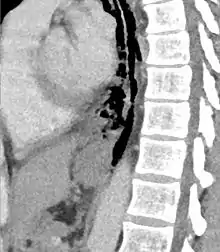

| Axial CT image through the upper chest showing extraluminal air (Pneumomediastinum) surrounding the trachea and esophagus | |

The diagnosis of Boerhaave's syndrome is suggested on the plain chest radiography and confirmed by chest CT scan. The initial plain chest radiograph is almost always abnormal in patients with Boerhaave's syndrome and usually reveals mediastinal or free peritoneal air as the initial radiologic manifestation. With cervical esophageal perforations, plain films of the neck show air in the soft tissues of the prevertebral space.

Hours to days later, pleural effusion(s) with or without pneumothorax, widened mediastinum, and subcutaneous emphysema is typically seen. CT scan may show esophageal wall edema and thickening, extraesophageal air, periesophageal fluid with or without gas bubbles, mediastinal widening, and air and fluid in the pleural spaces, retroperitoneum or lesser sac.